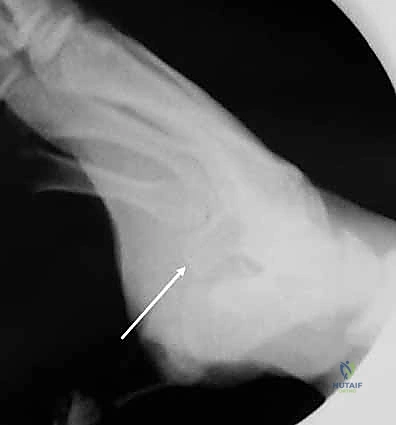

استئصال العظم السمسمي الظنبوبي الحل الدقيق لآلام إبهام القدم العنيدة مع الأستاذ الدكتور محمد هطيف

تخلص من آلام إبهام القدم المزمنة عبر استئصال العظم السمسمي الظنبوبي مع أ.د محمد هطيف بصنعاء. نعتمد أحدث تقنيات الجراحة المجهرية لضمان عودتك…